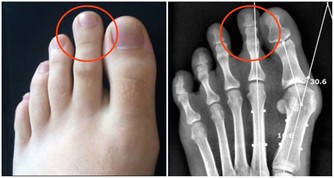

一、腳溝炎是什麼?

腳溝炎,是指腳指甲在受到外界的擦傷、刺傷、割傷後。因為沒有得到及時的處理,而受到局部的感染,細菌堆積,導致甲下發生膿腫,這是腳溝炎最主要的病因。此外,趾甲剪得太短或長期不剪趾甲、長期穿不合適的鞋子也會造成腳溝炎的發生。